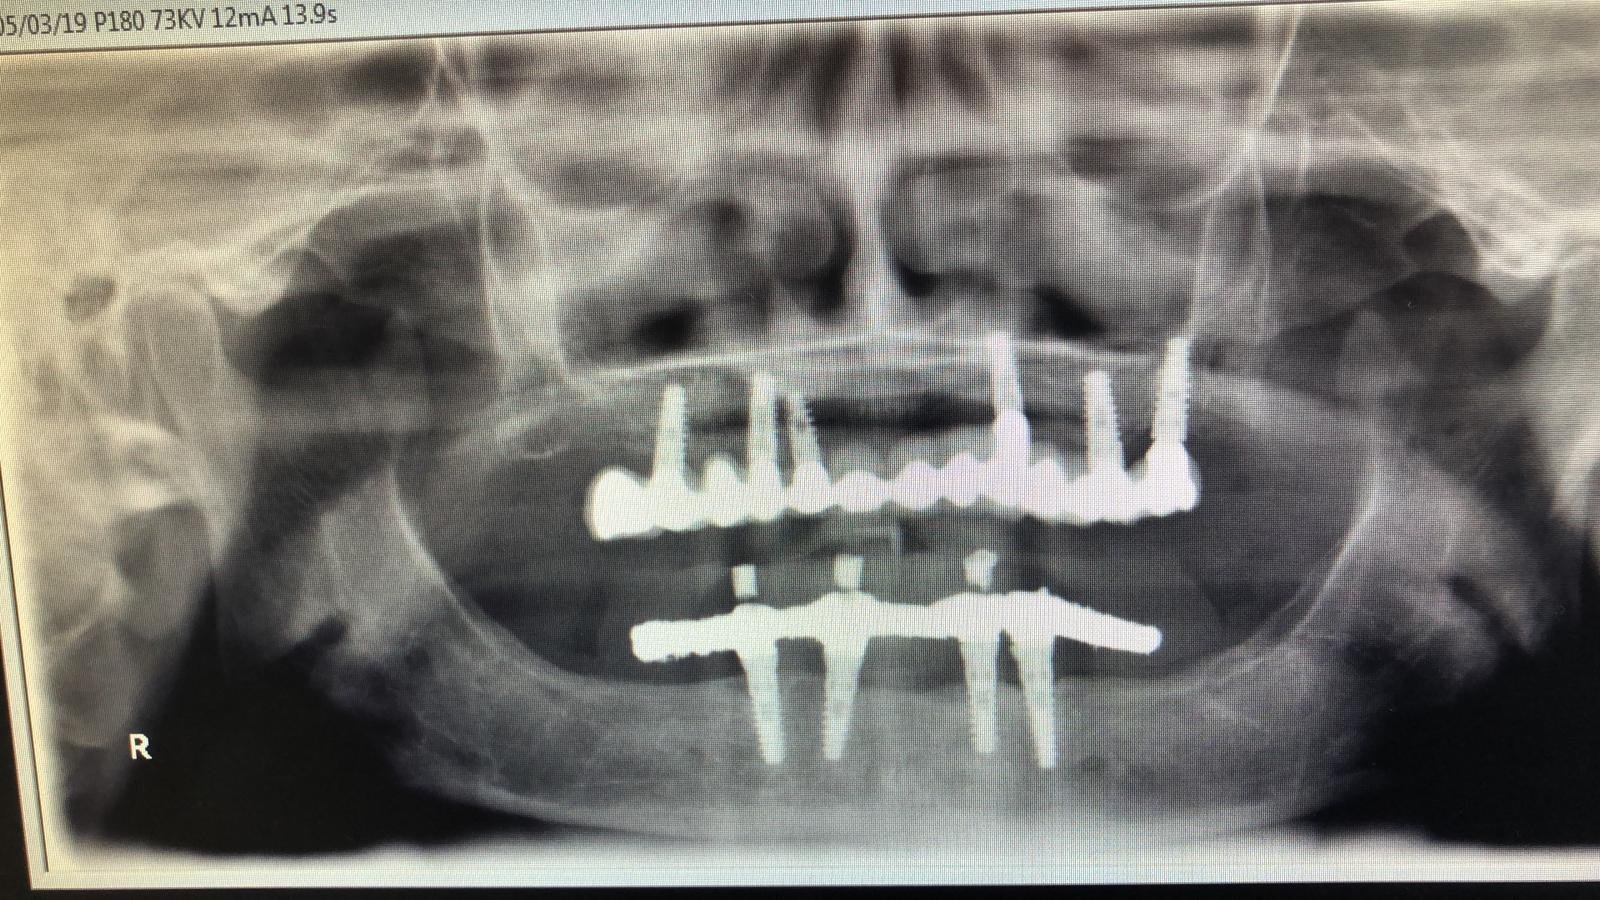

Buenas tardes, necesito que me ayuden a saber que implantes lleva nuestro paciente, en 24 y 46. También necesito saber que conexión tienen ya que le queremos cambiar las prótesis [...]

Hola, no sabemos que tipo de implantes son. La arcada superior es conexión intena hexagonal, de entre 3,5 y 4,2mm. La arcada inferior es conexión interna de 4,2, igual a [...]